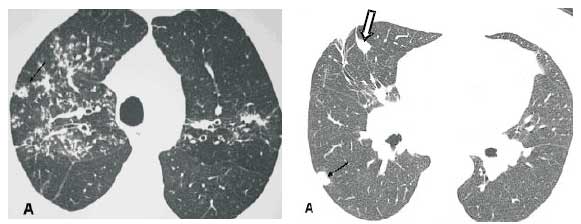

Nódulos. O padrão nodular é o mais freqüente na sarcoidose pulmonar. Os nódulos são geralmente pequenos e apresentam uma distribuição perilinfática, com envolvimento dos feixes peribroncovasculares, septos interlobulares, regiões centrolobulares subpleurais e ao longo das fissuras (Figuras 1 a 3). Nódulos cavitados ou de grandes dimensões, por vezes simulando neoplasias, podem ser encontrados em 15% a 25% dos casos (Figura 4)(1,4,7-10).

Opacidades em vidro fosco. Este padrão pode ser observado em 14 % a 83 % dos pacientes, tendendo a uma distribuição esparsa. Pode ocorrer isoladamente ou associado a sinais de fibrose pulmonar (Figura 5)(11-13).